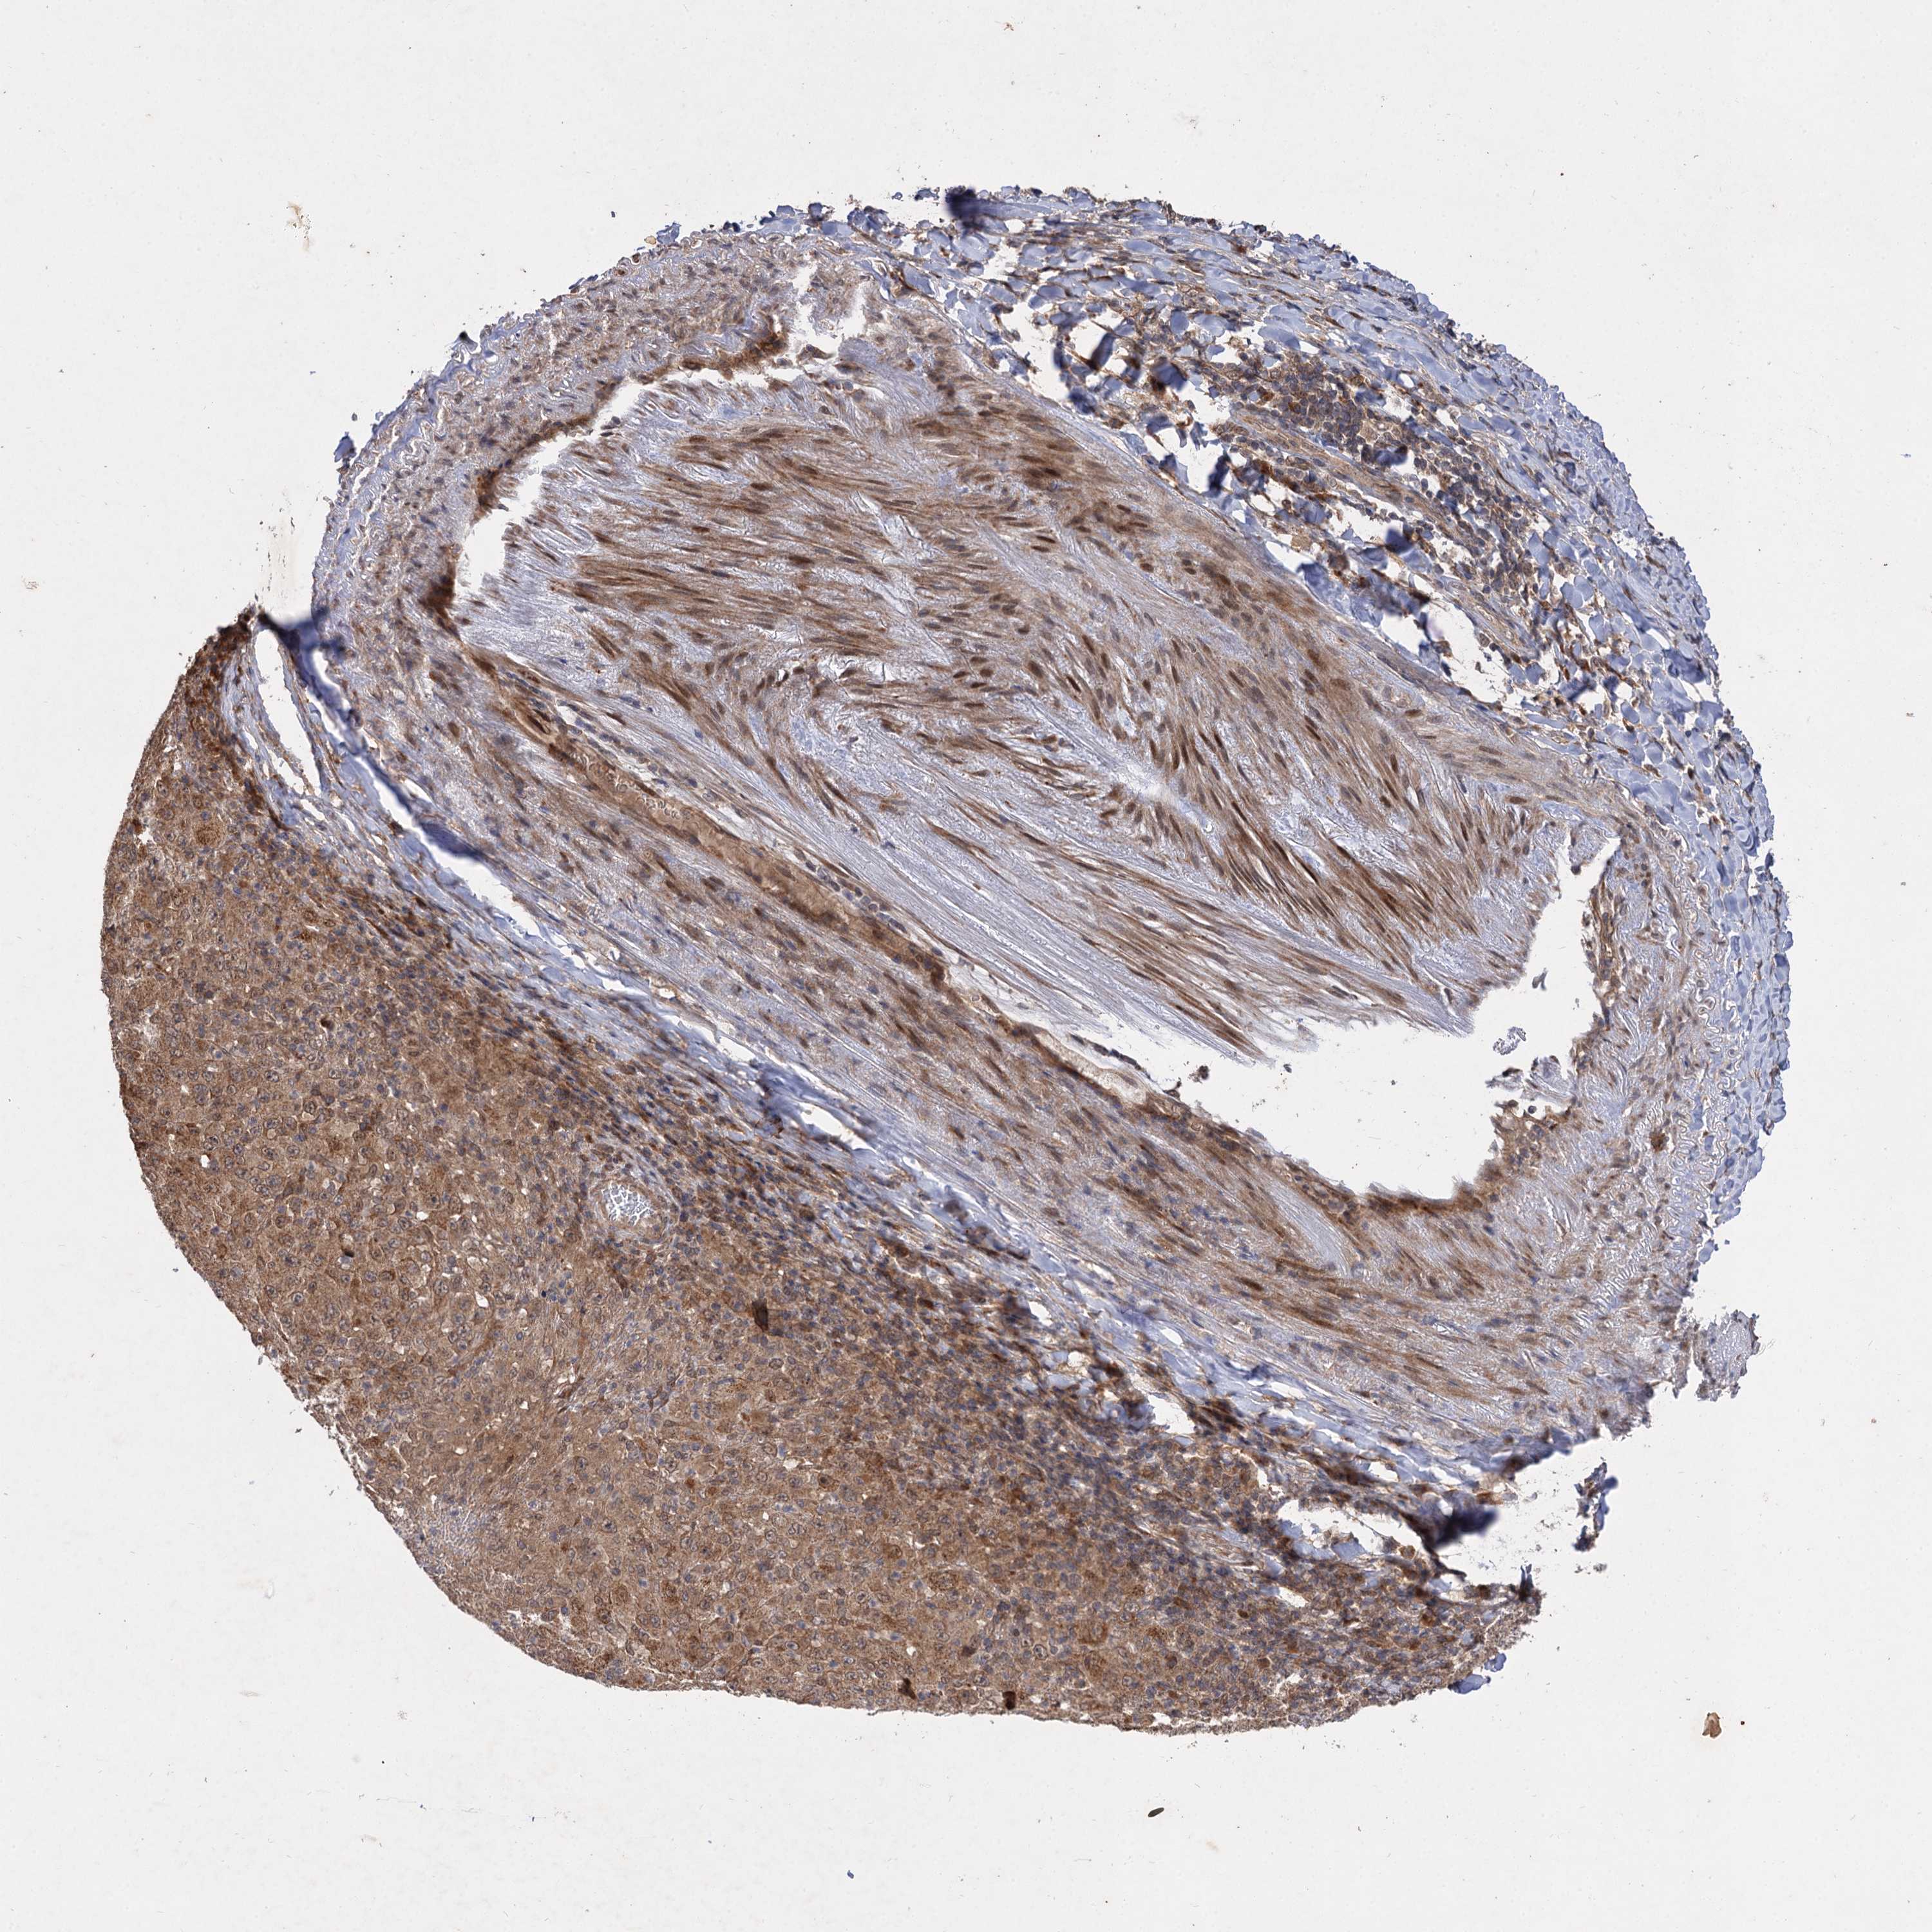

MELANOMA - Protein expressioni

A mouse-over function shows sample information and annotation data. Click on an image to view it in a full screen mode. Samples can be filtered based on level of antibody staining by selecting one or several of the following categories: high, medium, low and not detected. The assay and annotation is described here.

Note that samples used for immunohistochemistry by the Human Protein Atlas do not correspond to samples in the TCGA dataset.

Antibody stainingi

Antibody staining in the annotated cell types in the current human tissue is reported as not detected, low, medium, or high, based on conventional immunohistochemistry profiling in selected tissues. This score is based on the combination of the staining intensity and fraction of stained cells.

Each image is clickable and will lead to virtual microscopy that enables deeper exploration of all samples and also displays staining intensity scores, fraction scores and subcellular localization as well as patient and tissue information for each sample.

Antibody HPA038850

Antibody HPA038851

Staining

High

Medium

Low

Not detected

Intensity

Strong

Moderate

Weak

Negative

Quantity

>75%

75%-25%

<25%

None

Location

Nuclear

Cytoplasmic/membranous

Cytoplasmic/membranous,nuclear

Malignant melanoma, NOS

Malignant melanoma, Metastatic site